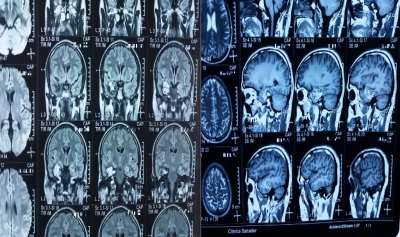

Drept mărturie stă experiența unui tânăr român, în vârstă de 34 de ani, din Marea Britanie, care s-a prezentat la medic cu deficit motor controlateral și crize de epilepsie. Tânărul începuse să aibă probleme cu partea stanga a corpului, cauza fiind tumora localizată în emisfera dreaptă a creierului. A fost diagnostigat în Marea Britanie cu o formațiune tumorală (cavernom) cerebrală temporală dreaptă profundă. Medicii de acolo au programat intervenția după o perioadă lungă de timp, din cauza încărcăturii din sistemul de sănătate, în pofida situației grave în care se afla tânărul.

În căutarea salvării, pacientul a ajuns la dl. Dr Ovidiu Grămescu, medic primar Neurochirurgie și Șeful Secției Neurochirurgie din cadrul Spitalului Clinic Sanador. Și-a făcut toate investigațiile preoperatorii și s-a pregătit pentru o operație dificilă, ce urma să fie efectuată sub lentila minuțioasă a microscopului operator Zeiss Kinevo 900 – unic în România, echipament chirurgical de calitate superioară, sistem de neuronavigatie și aspirație tumorală.

Medicii au folosit neuronavigația pentru a ajunge la tumora „îngropată” profund în interiorul creierului și și-au folosit toată măiestria pentru a proteja structurile cerebrale care. În cazul unei asemenea intervenții, au un risc mare de afectare. Din echipa medicală Sanador condusă de dr. Ovidiu Grămescu au facut parte, Dr. Ionut Florin Luca-Husti, Medic primar Neurochirurgie, Dr. Ioana Gramescu, Medic primar Anestezie și Terapie Intensivă, asistenta Silvia Șarpe, la instrumentar, și o asistentă la anestezie.